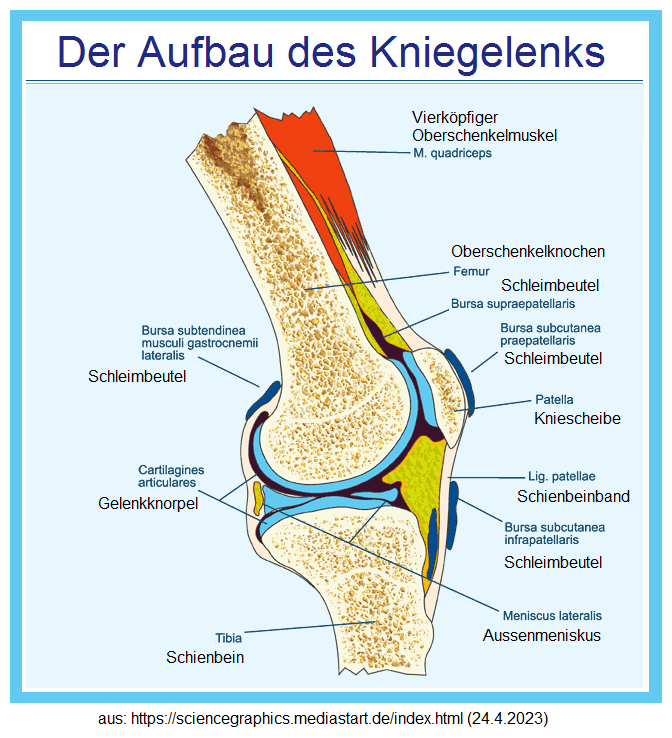

Knie schmerzt [1] - Knie im Modell seitlich [2] und frontal [3] - Knie Schema mit dem Querschnitt [4]

[4] Knie Schema Querschnitt: https://sciencegraphics.mediastart.de/index.html